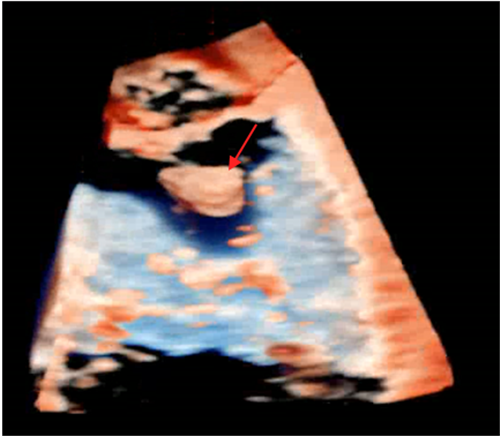

术中使用二枚二尖瓣钳子完成手术

2月2日上午,贺先生在全麻下进行介入手术。经手术团队充分缜密的术前准备,成功为患者植入2个二尖瓣夹。术后患者反流情况明显改善,跨瓣平均压差4mmHg,左上和右上肺静脉逆流明显改善,反流改善明显。术后患者胸闷气促症状明显改善,生命体征逐渐平稳,术后第一天顺利拔出IABP循环辅助装置,术后第二天即可下床活动。贺先生出院当日,热泪盈眶地说:“我以为这个年跨不过去了,感谢你们给了我第二次生命,让我重获新生,可以回家过年了。”